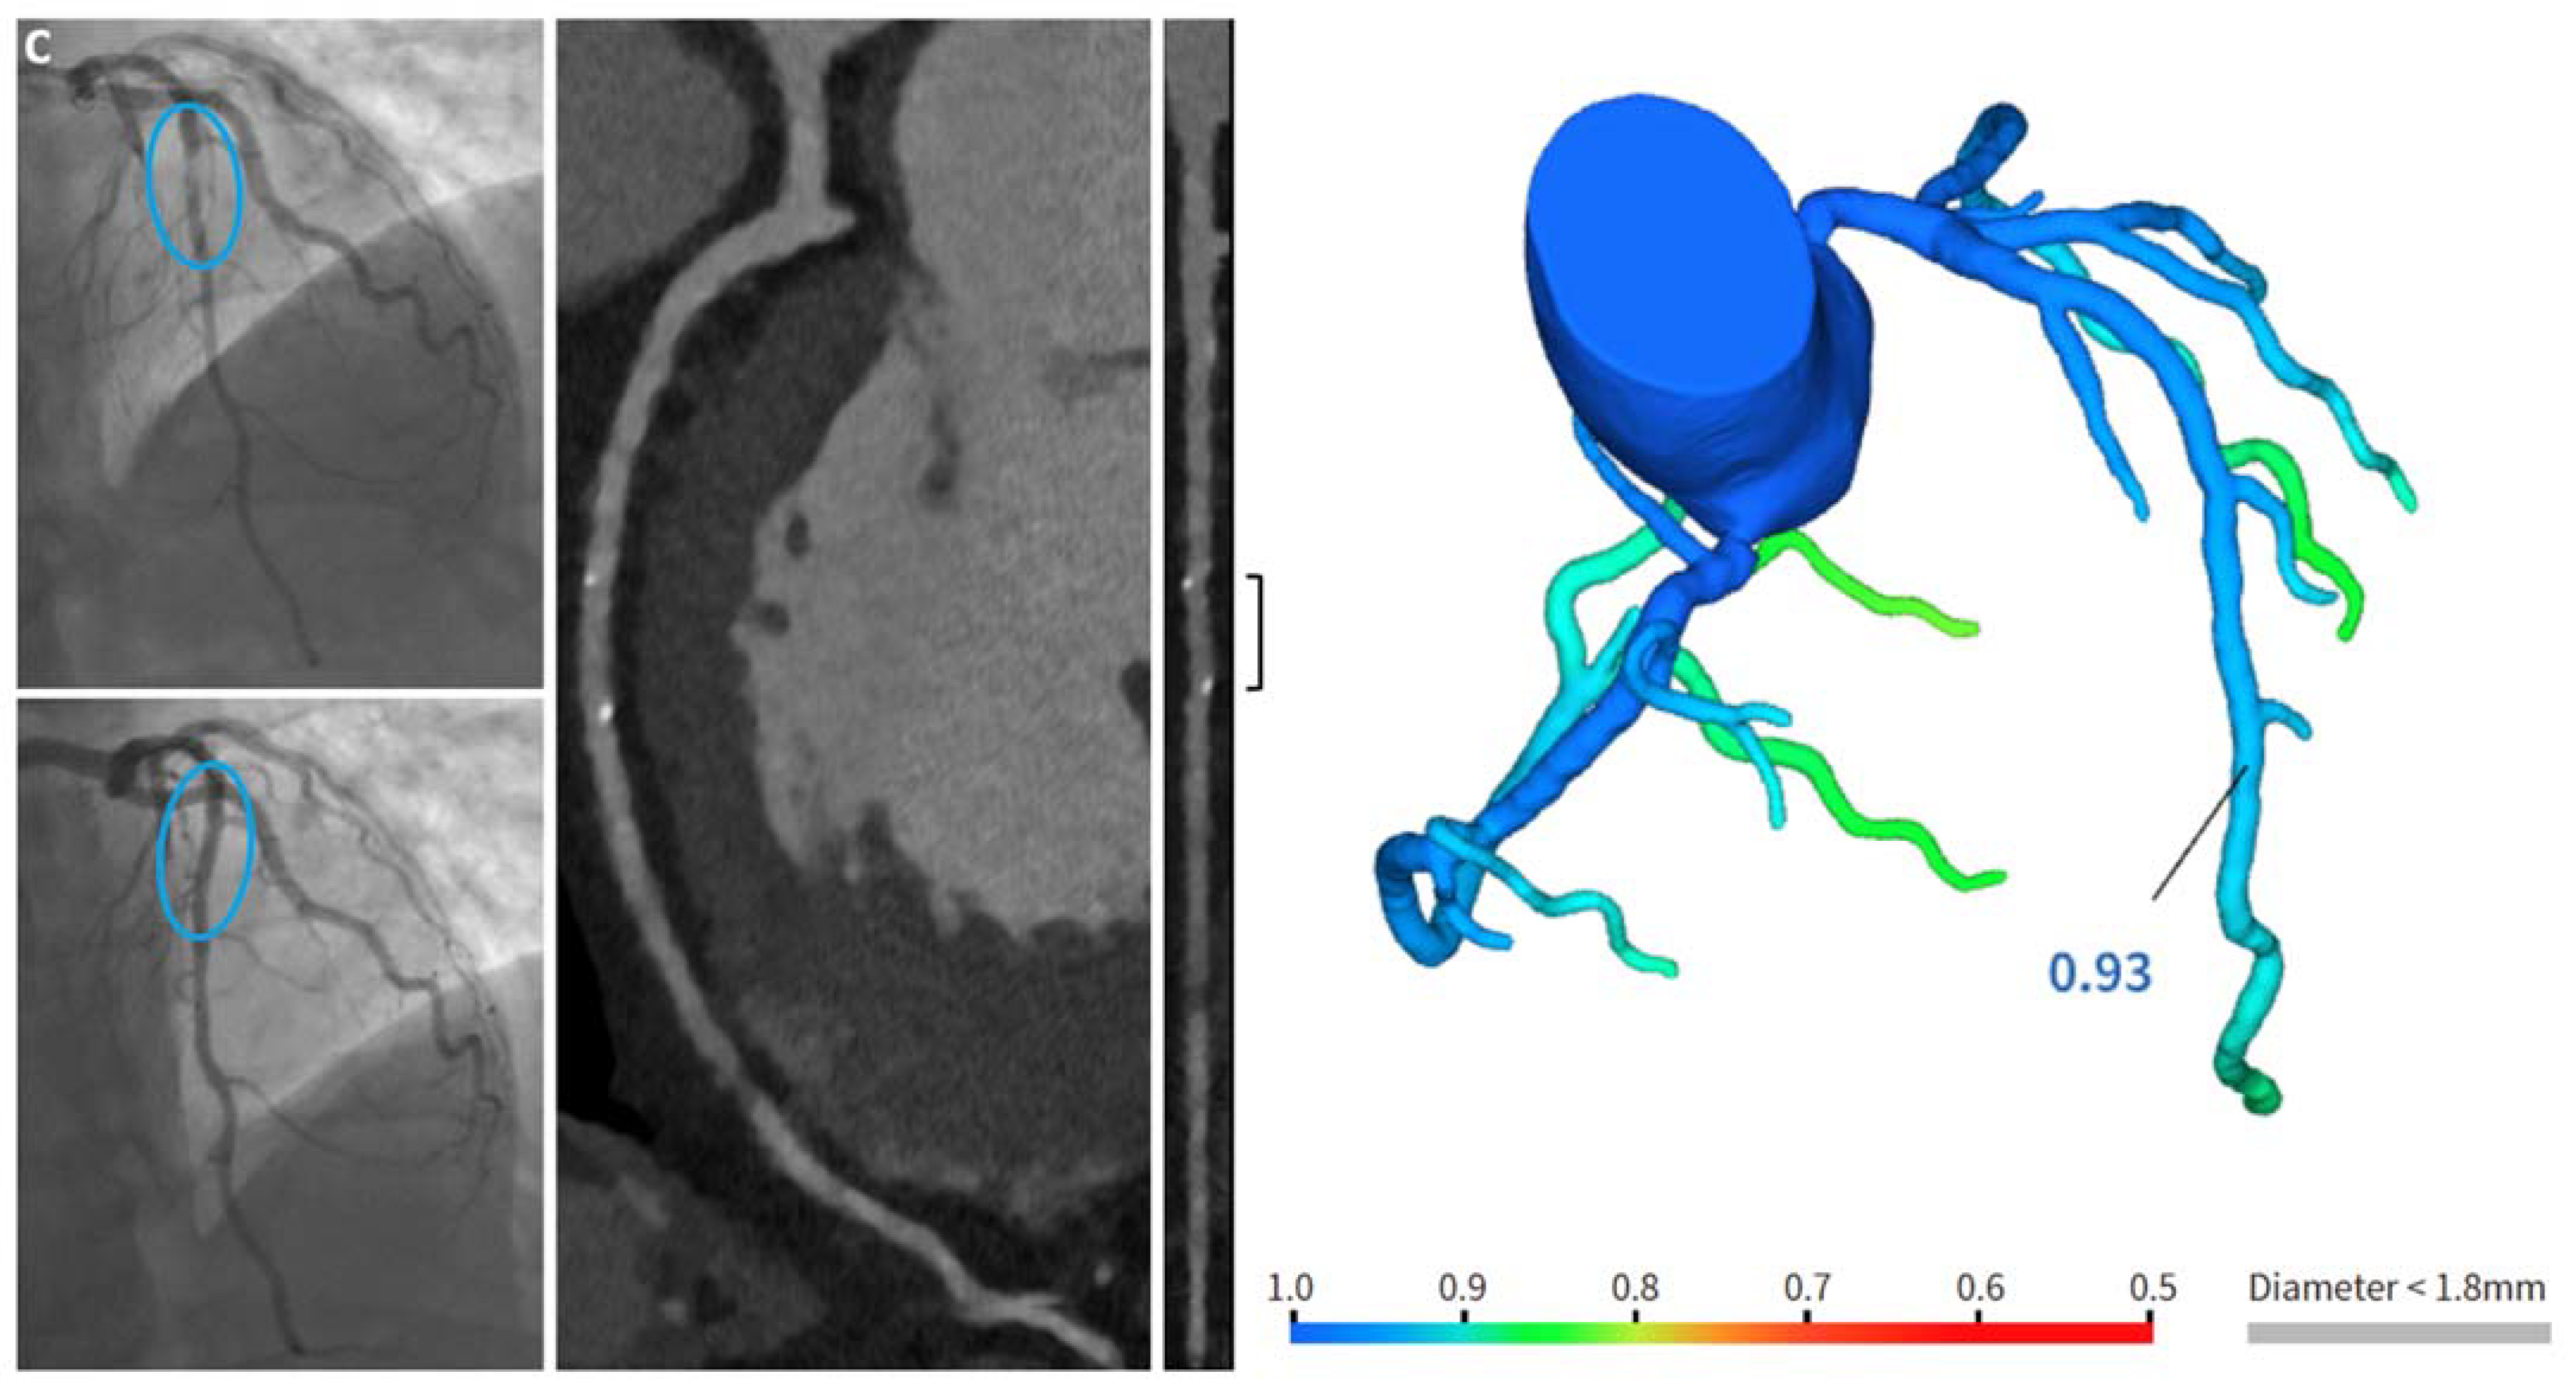

- C.

- A patient with a focal culprit plaque on the LAD, treated by one RMS (Magmaris® 2.5 × 25 mm).